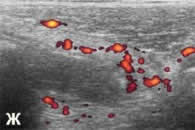

| д, е, ж - гангренозный (подтверждено на

операции) аппендицит у 8-летнего ребенка. Нарушена дифференцировка

слоев аппендикса, но при ротации датчика удается получить

структуру вытянутой формы, прилежащие к ней ткани гиперемированы

(отросток был окутан сальником). |